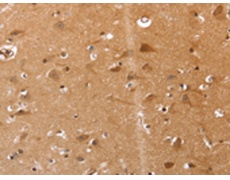

IHC positive control: |

Human brain and Human renal cancer |

IHC Recommend dilution: |

25-100 |